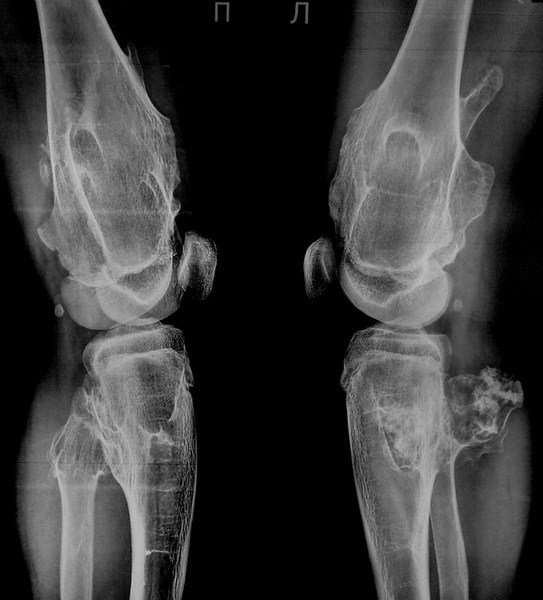

На изображении видно, что болезнь проходит через несколько стадий развития, поэтому важно своевременно распознать ее ранние признаки.

Это могут быть уплотнения на суставных поверхностях. Наличие таких образований и разрастание хрящевой ткани подтверждается рентгеном, хотя иногда используется компьютерная томография.

Внешние симптомы. У больных ахондроплазией аномально низкий рост, укороченные конечности, непропорциональный размер туловища. У многих людей наблюдается деформация в грудном отделе позвоночника, поражение коленных суставов. Пальцы на руках могут иметь одинаковую длину.